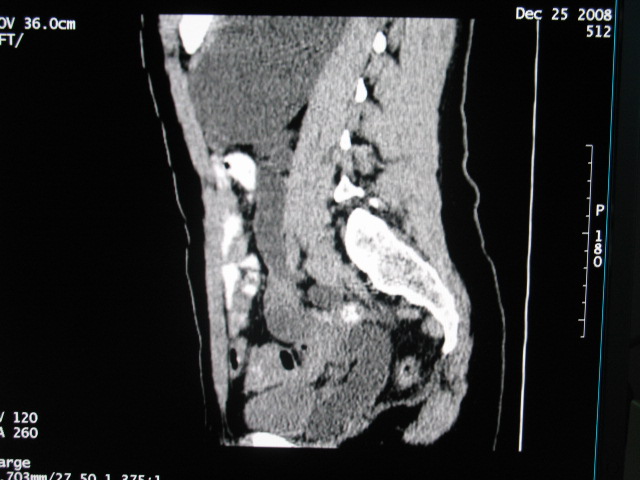

女,28岁,自觉腹部包块一年余

左侧为扩张的输尿管,一直延续到膀胱,那么它的上端应该是扩张的肾盂,但是在他的下方我们看到一个比较正常的肾,所以考虑左侧重复肾盂输尿管畸形。

考虑左侧双肾盂双输尿管畸形,其中一输尿管末端梗阻(不排除异位开口可能)并相应之肾盂及输尿管明显扩张积水。

左侧重复肾、双输尿管畸形。重复肾一般上位肾发育不良,易合并积水。

考虑左侧双肾盂双输尿管畸形,其中一输尿管末端梗阻(不排除异位开口可能,不知病人有无不自觉溢尿,有可能开口于阴道或宫颈,也可下端为盲端)并相应之肾盂及输尿管明显扩张积水。

术后证实是左侧双肾盂双输尿管畸形,巨输尿管巨肾盂症